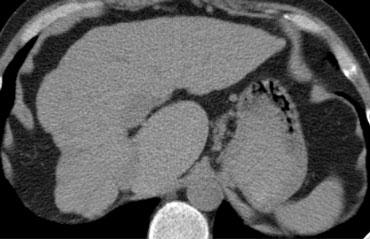

Thùy đuôi

Thùy đuôi hay phân thùy I nằm ở phía sau.

Thùy đuôi có đặc điểm giải phẫu khác biệt so với các thùy khác ở chỗ nó thường có các kết nối trực tiếp với tĩnh mạch chủ dưới thông qua các tĩnh mạch gan riêng biệt, tách rời khỏi các tĩnh mạch gan chính.

Thùy đuôi có thể được cấp máu bởi cả nhánh phải và nhánh trái của tĩnh mạch cửa.

Hình ảnh CT này của một bệnh nhân xơ gan với teo nặng thùy gan phải, thể tích thùy gan trái bình thường và phì đại thùy đuôi.

Do có nguồn cấp máu khác biệt, thùy đuôi không bị ảnh hưởng bởi quá trình bệnh lý và phì đại để bù đắp cho sự mất mát của nhu mô gan bình thường.